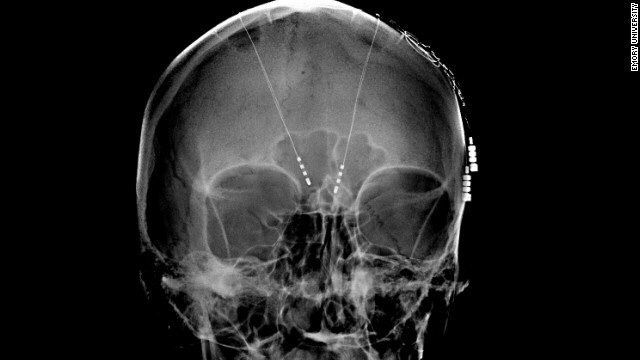

Dr. Collins’s experimental contraption uses “Precision Deep Brain Stimulation”, and uses implanted electrodes to produce electricity which regulates the human brain. The system can “recognize” specific patterns of brainwaves associated with depressive behaviors, and regulate the electric impulses.

Deep Brain Stimulation (DBS) involves the surgical implanting of electrodes into the brain, similar to those used in lab rats. These electrodes are connected via an insulated wire, connecting to a neurostimulator implanted under the skin. The neurostimulator regulates the electronic impulses being sent deep into the brain. This experimental technology has been known to produce life altering side effects, including change in human behavior and total change in personality. The change is not always to the patients liking, and unpredictably dependent upon the patient.